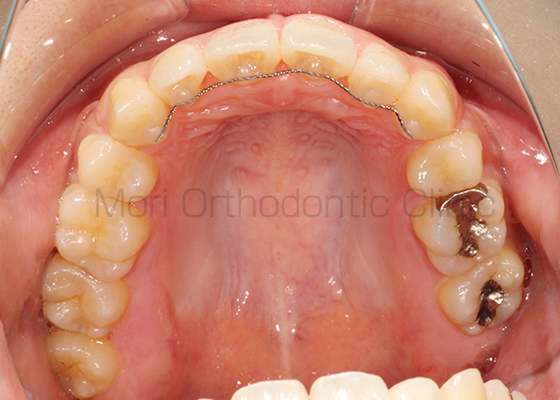

術前

術後

| 主訴 | 歯並び、八重歯 |

|---|---|

| 診断名 | AngleⅡ級叢生 |

| 年齢 | 30歳2か月 |

| 治療装置 | Multi-Bracket(表側矯正)、CARRIERE DISTALIZER |

| 抜歯部位 | 14,24,35,45 |

| 治療期間 | 2年1か月 |

| 治療費 | 825,120円(税込) |

| リスク・副作用 | 矯正治療による歯の移動に伴う痛み、歯根吸収、歯肉退縮、虫歯 |